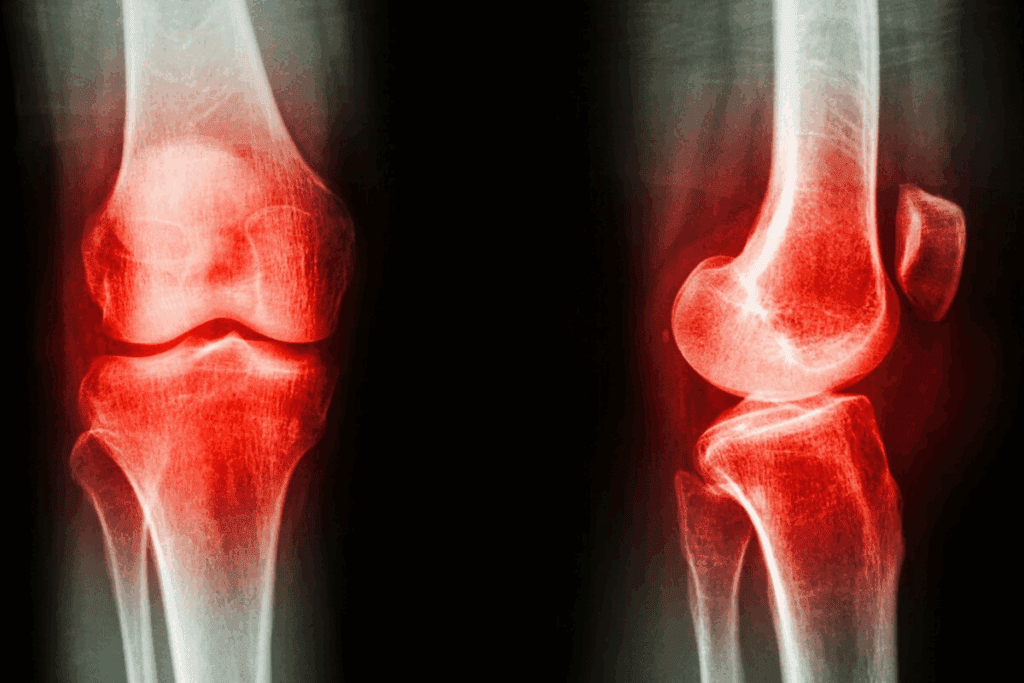

The knee joint is complex and heavily used, making it prone to pain and injuries. Knowing about knee pain is key to managing and treating it effectively.

Anatomy of the Knee Joint

The knee joint connects the femur (thigh bone) to the tibia (shin bone). It’s stabilized by ligaments and supported by muscles and tendons. This joint allows for flexion and extension, enabling a wide range of movements.

The key components of the knee joint include:

- Ligaments: Providing stability and support

- Tendons: Connecting muscles to bones

- Meniscus: Cartilage structures that cushion the joint

- Synovial membrane: Producing fluid that lubricates the joint

Common Types of Knee Pain

Knee pain can be categorized into several types based on its causes. Knowing these categories is important for the right treatment.

Imaging tests are vital for diagnosing knee pain. X-rays check bone health and look for fractures or wear and tear. Magnetic Resonance Imaging (MRI) shows soft tissue details, like ligaments and cartilage, helping spot injuries or conditions like tendinitis.